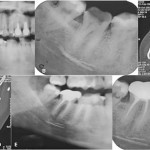

Diagnosi e terapia: parestesia del nervo alveolare inferiore

Diagnosi differenziale con cone beam computer tomography della parestesia del nervo alveolare inferiore in seguito a trattamento endodontico: case report

Differential diagnosis of endodontic-related inferior alveolar...